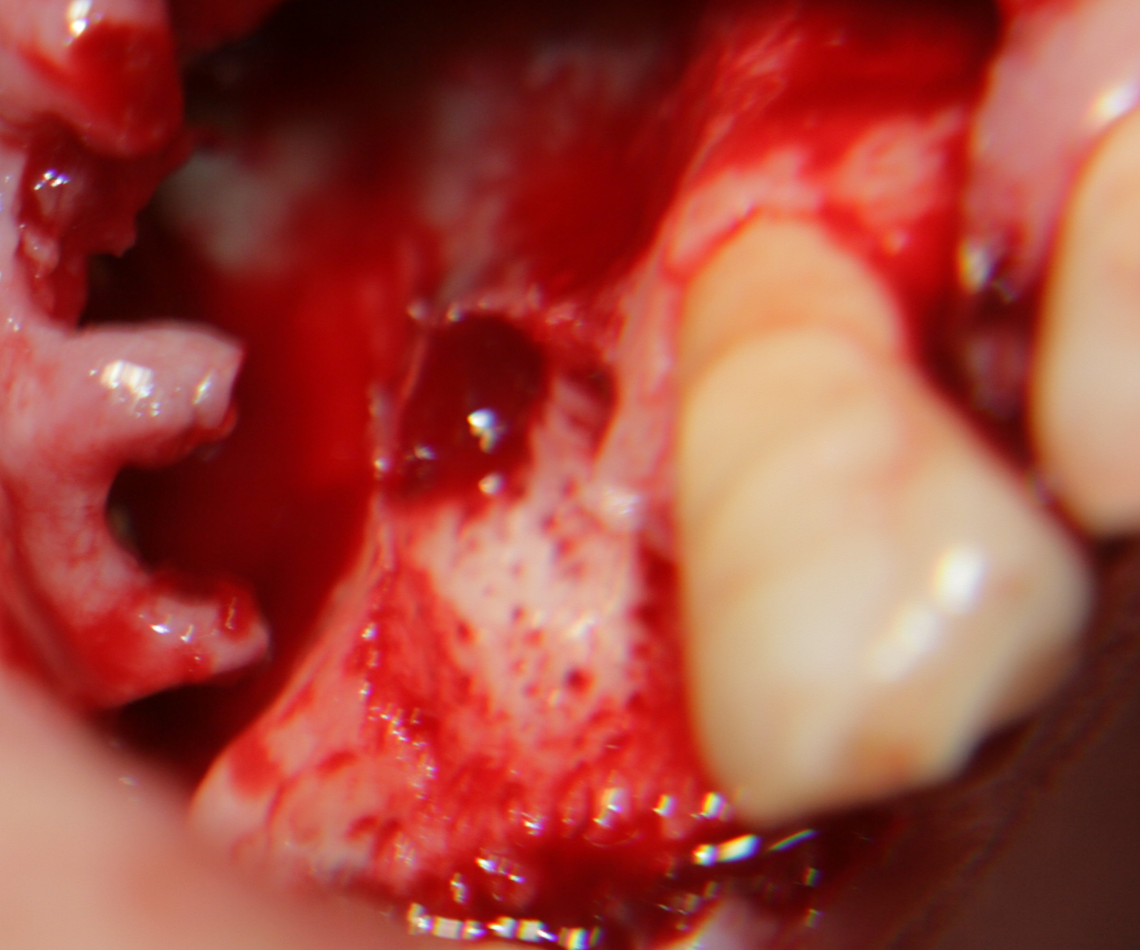

Отворен максиларен синус в началото на интервенцията. Случаят е интересен със следното - твърде атипична форма на трепанационния отвор. На какво се дължи на това - на лошо планиране на оперативния достъп или на нещо друго? Дължи се на факта, че отначало въпросната намеса беше планирана като балонен синуслифт; за съжаление обаче мембраната на синуса се разкъса и надуването на балона стана невъзможно.